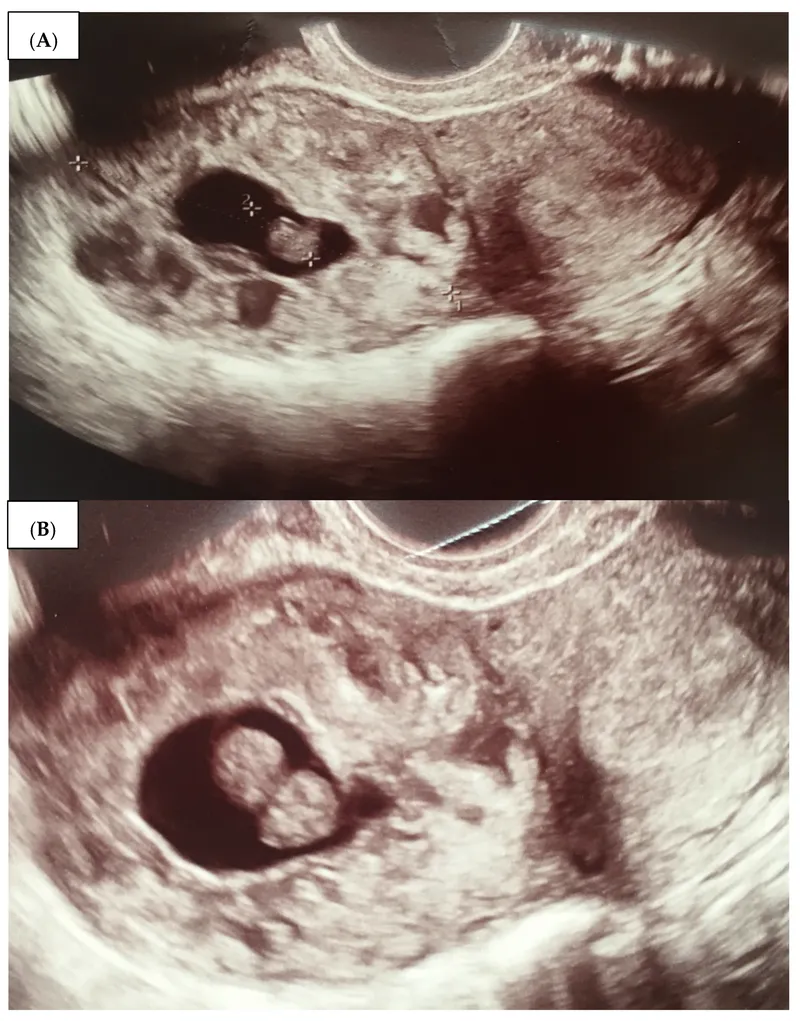

- Positive: FHS (Doppler 8-10 wks; Fetoscope 18-20 wks), fetal movements (examiner >20 wks), USG (cardiac activity 6-7 wks).

- USG CRL (1st trimester - gold standard); BPD, HC, AC, FL later.